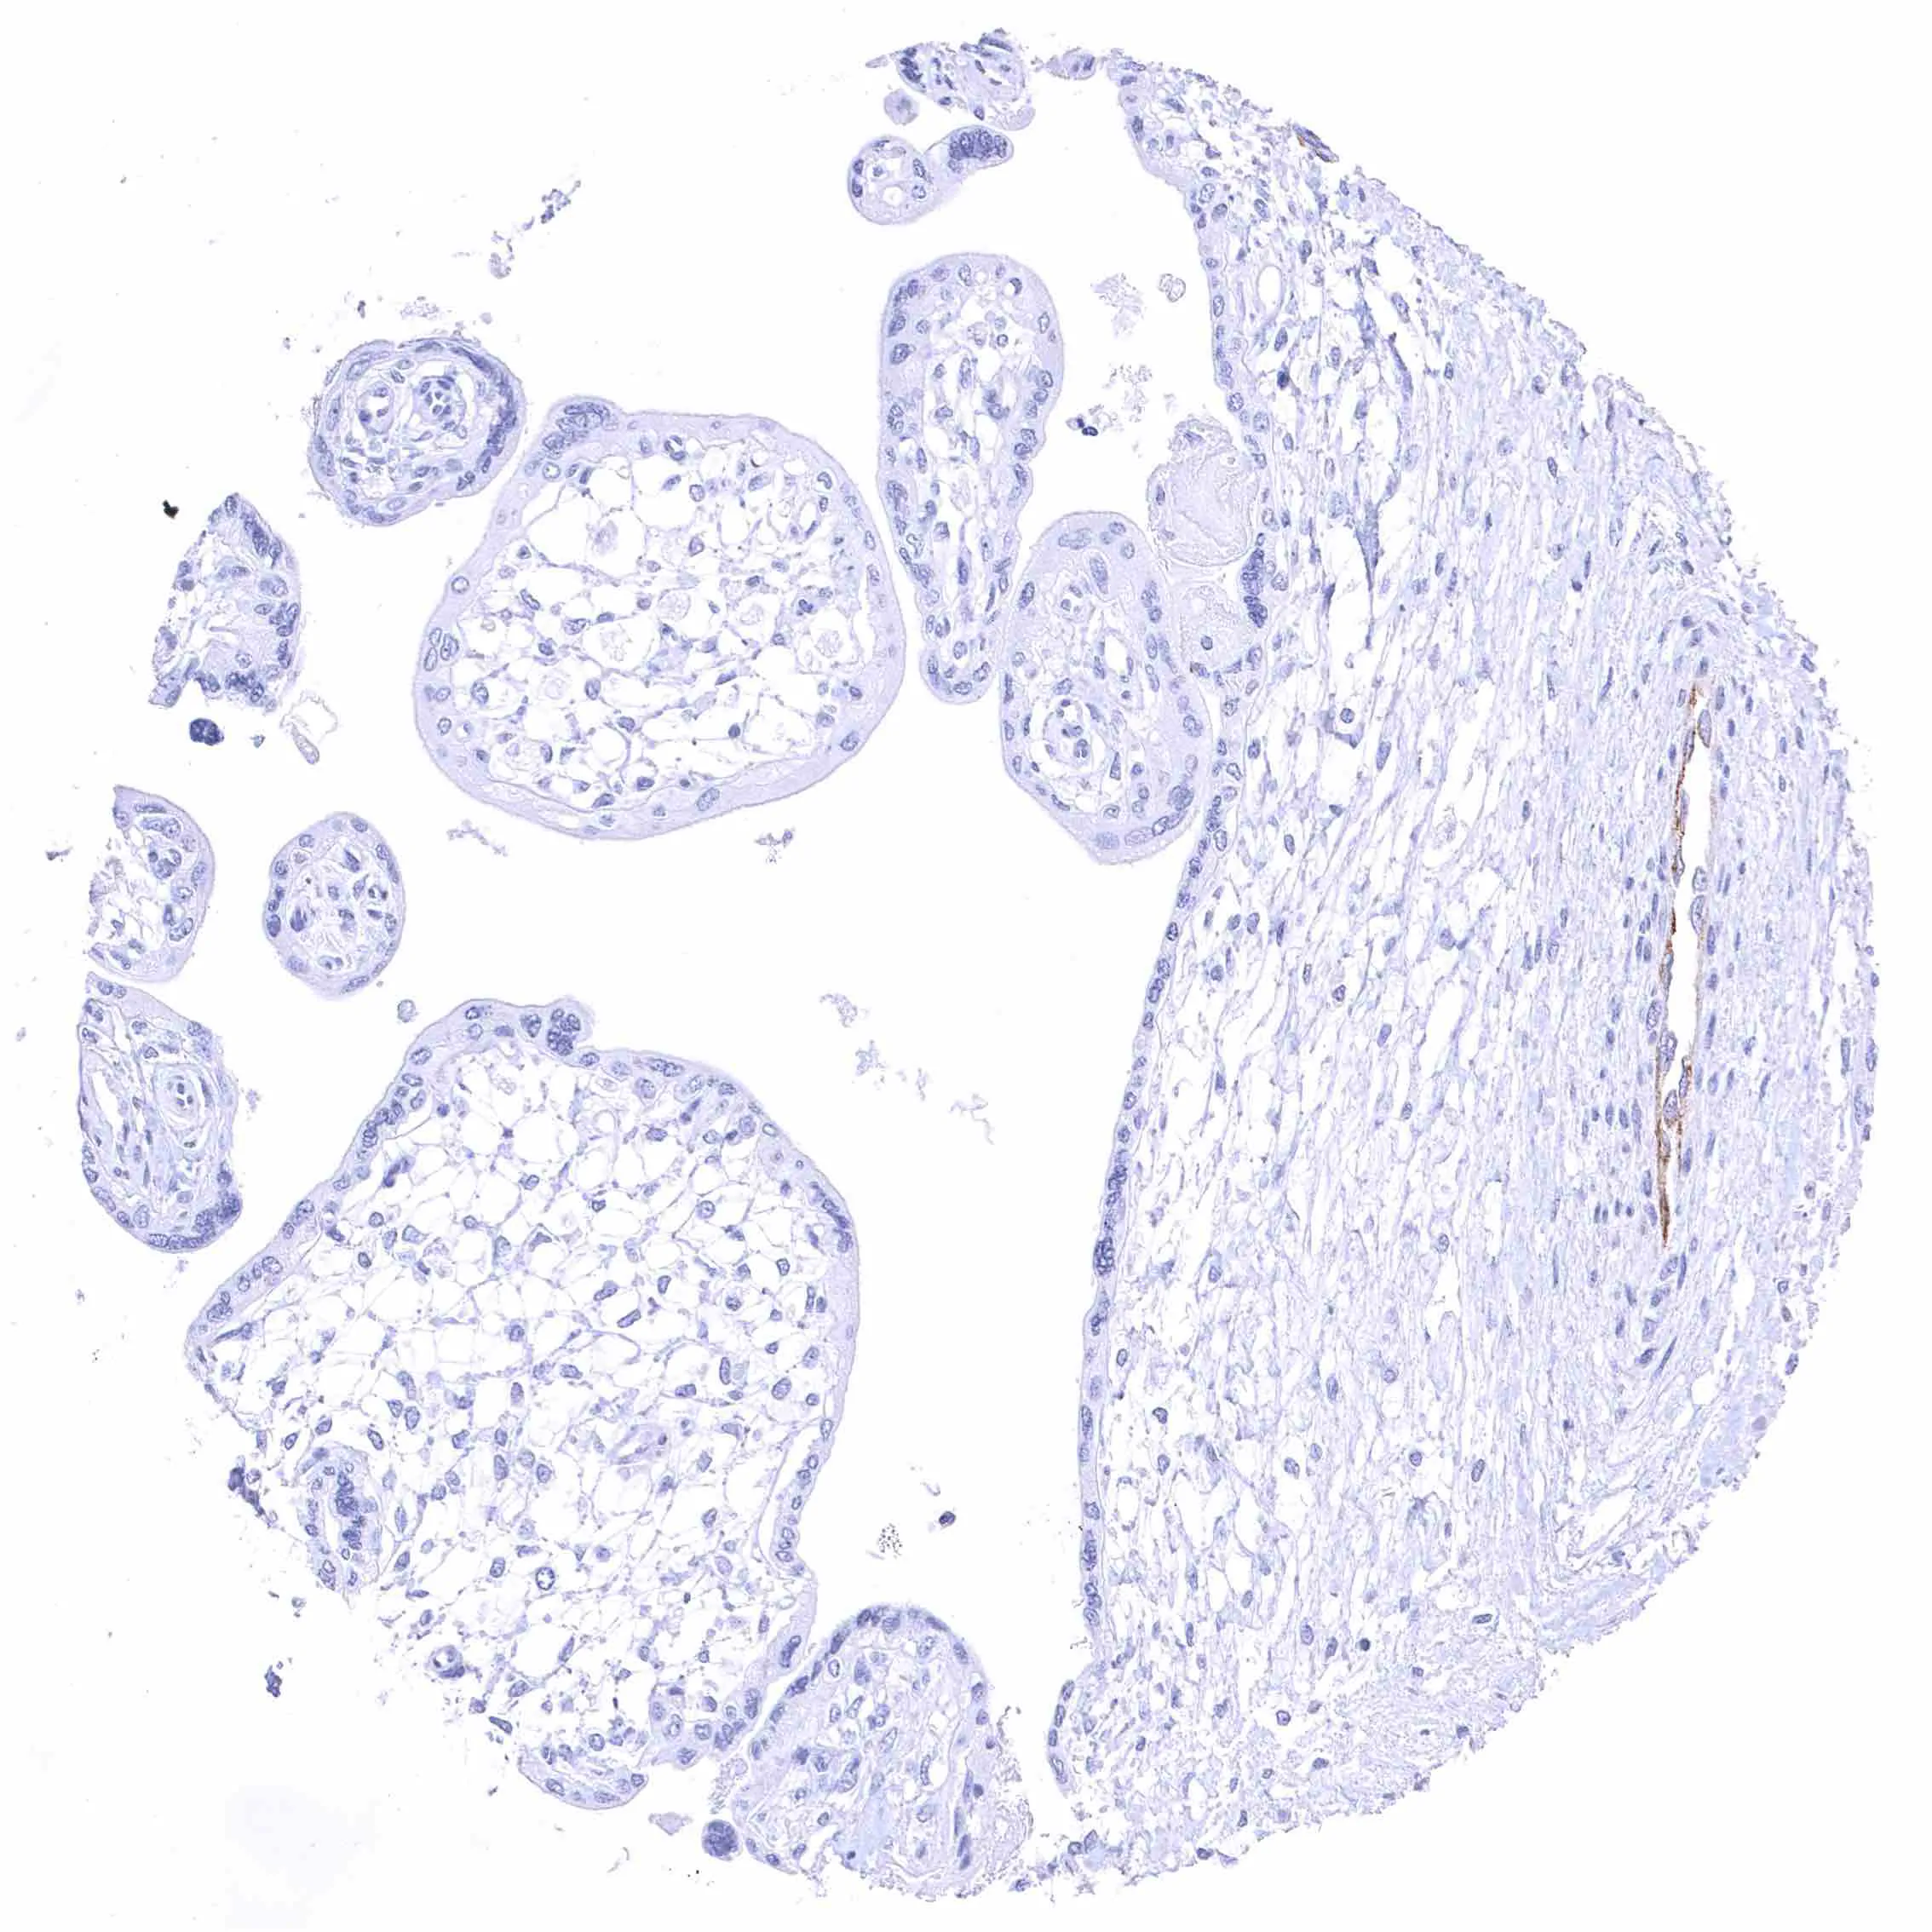

Prostate